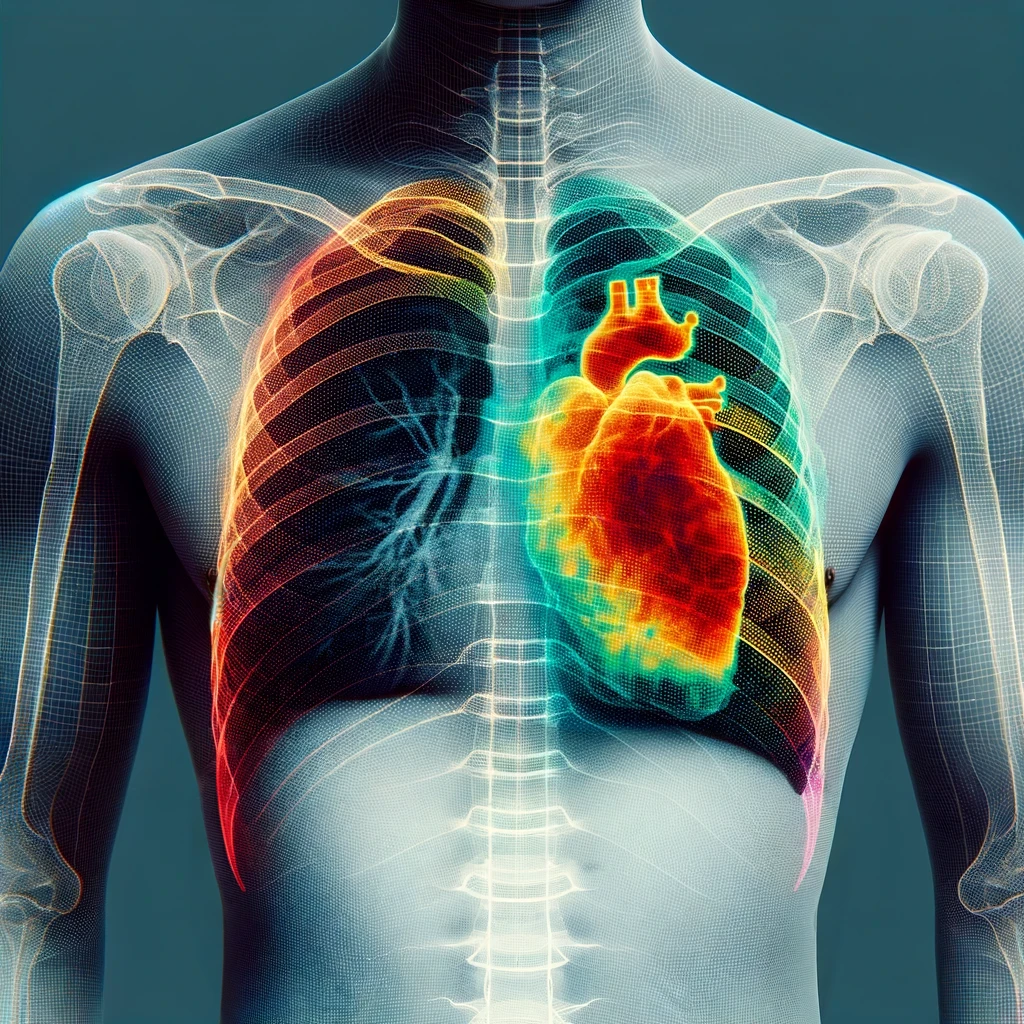

La medicina tradicional está experimentando una transformación gracias a la integración de soluciones tecnológicas avanzadas. XOR-Ray es pionero en este cambio, utilizando algoritmos de aprendizaje automático y procesamiento de imágenes para analizar radiografías. Este enfoque no solo mejora la precisión de los diagnósticos sino que también facilita recomendaciones de tratamiento personalizadas basadas en patrones identificados por la IA.